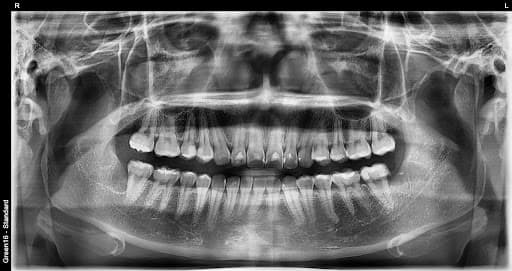

横生智齿

横向生长会挤压 相邻的牙齿

引发炎症

忽视智齿会导致 牙龈肿胀和发生炎症

复杂的阻生智齿 - 即使深埋在牙龈中也没问题

贴近神经的智齿 - 无需担心神经损伤,安全拔除

水平阻生智齿 - 即使是横向生长的困难案例也可以处理

即使没有疼痛,智齿也可能在牙龈内部引起炎症、蛀牙和咬合不齐。3D CT精确诊断后,如果不早期拔除,可能会出现急性炎症、邻牙损伤和颞下颌关节问题等。年轻时拔除恢复更快,并发症风险更低。